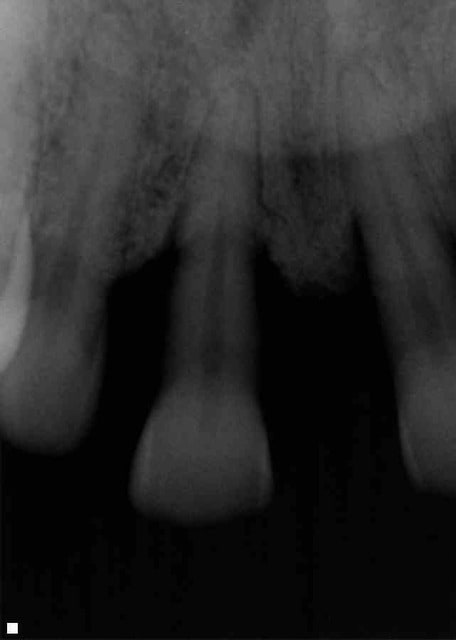

- Patient 53 ans, non fumeur, bonne santé générale.

- Consulte pour 11 "légèrement mobile et qui vient toucher sa lèvre inférieure".

la mobilité est probablement d'origine parodontale.

ca sent la parodontite agressive.

visiblement peu de plaque et de tartre, et le patient s'est rendu compte de la progression de la maladie parodontale, ce qui veut dire que c'est assez rapide. Il faudrait quand meme la pano et un charting pour confirmer le diagnostic.